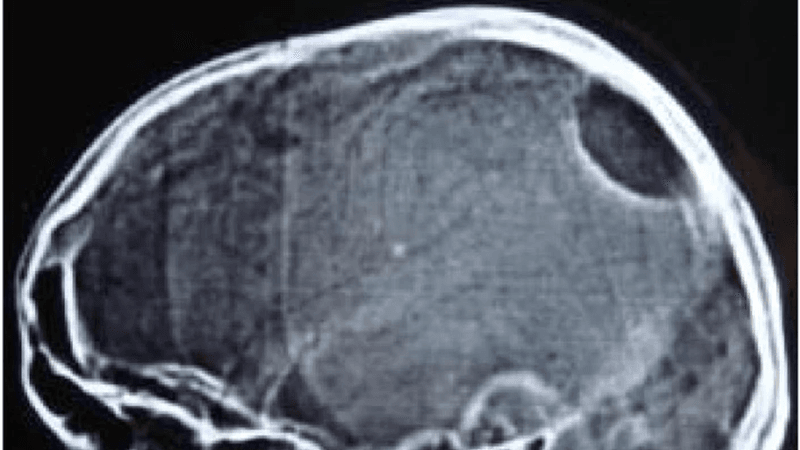

But if it’s partially genetic, the team reasoned, then perhaps they could find signs of the condition turning up during fetal development. They analyzed 39 MRI scans taken of living fetuses at around 25 weeks gestation – the scans had already been taken regardless of the study, not specifically for it – to see if they could spot any differences in brain structure between children who would go on to develop autism and children who wouldn't.

Their hunch paid off: the scans of fetuses that went on to receive an ASD diagnosis showed significant differences in an area of the brain known as the insular lobe. That’s a region responsible for things like self-awareness (both physical and emotional), social abilities, and behavior regulation – all things people with ASD can have real trouble with.

“Our results suggest that an increased volume of the insular lobe may be a strong prenatal MRI biomarker that could predict the emergence of ASD later in life,” explained Ortug.

Scans from children with ASD also showed an enlarged amygdala and hippocampal commissure.